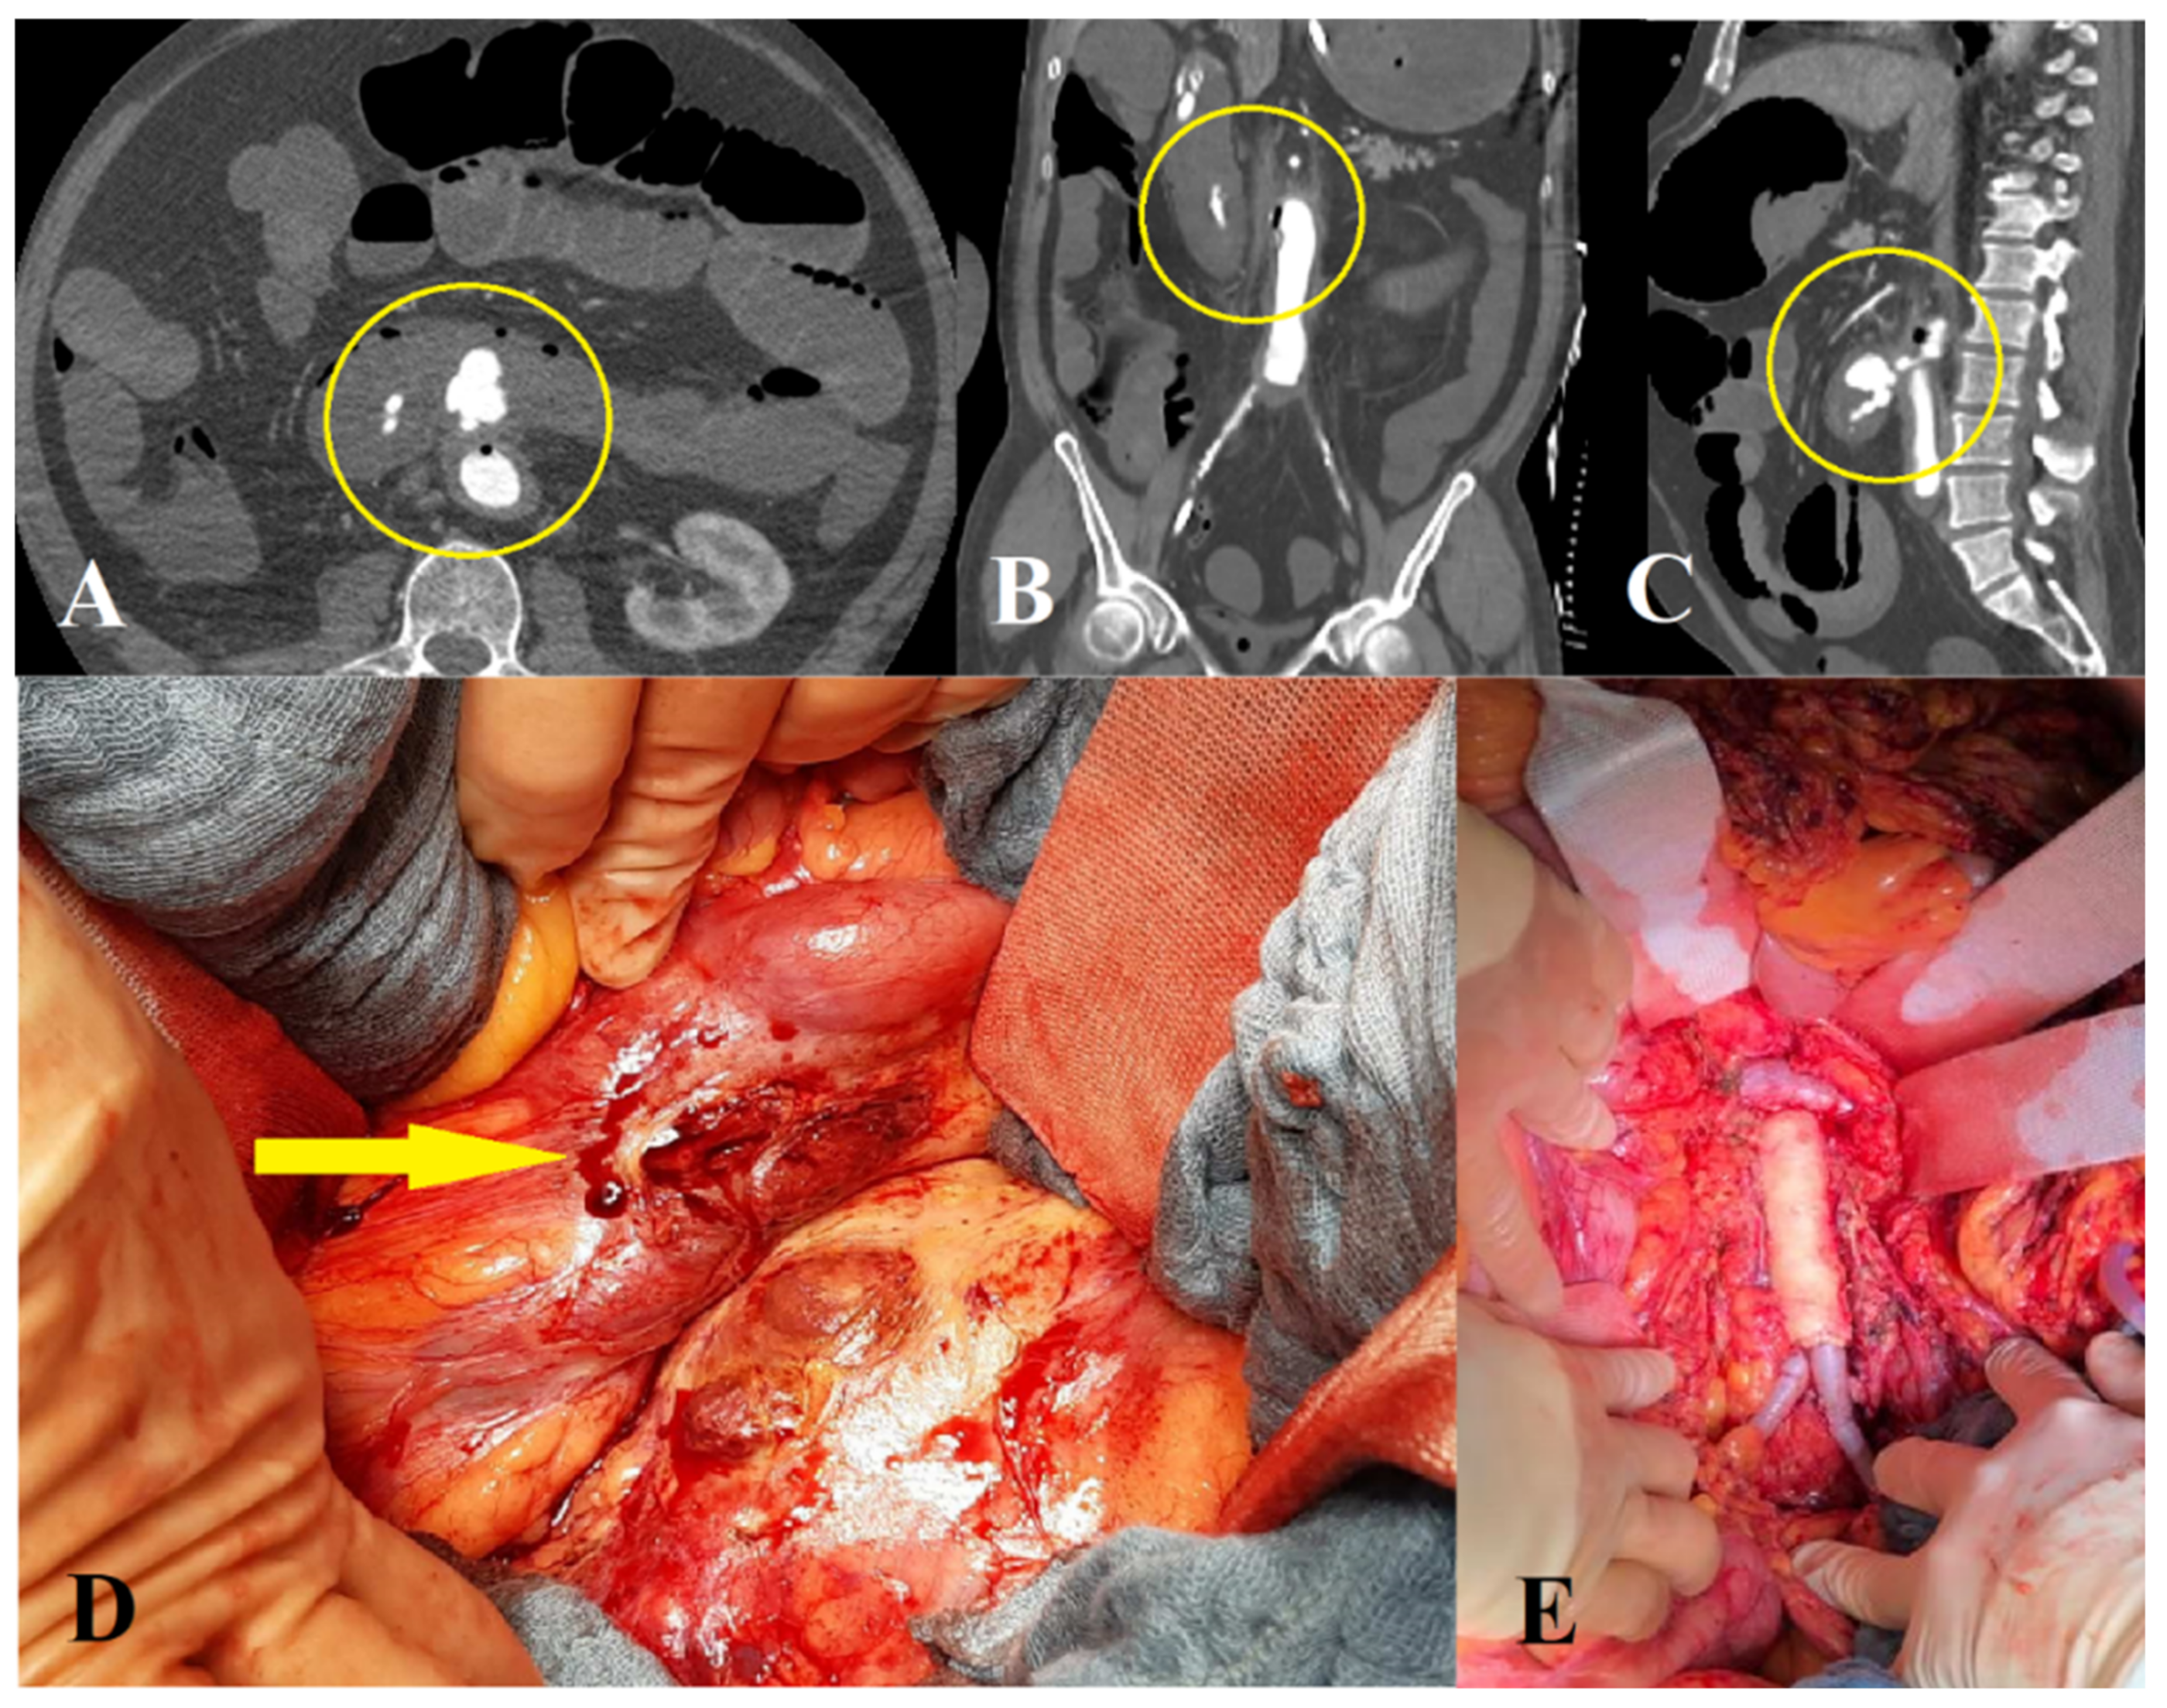

3.2.1. Open Surgical Repair

3.2.2. Endovascular Repair

3.2.3. Hybrid Repair